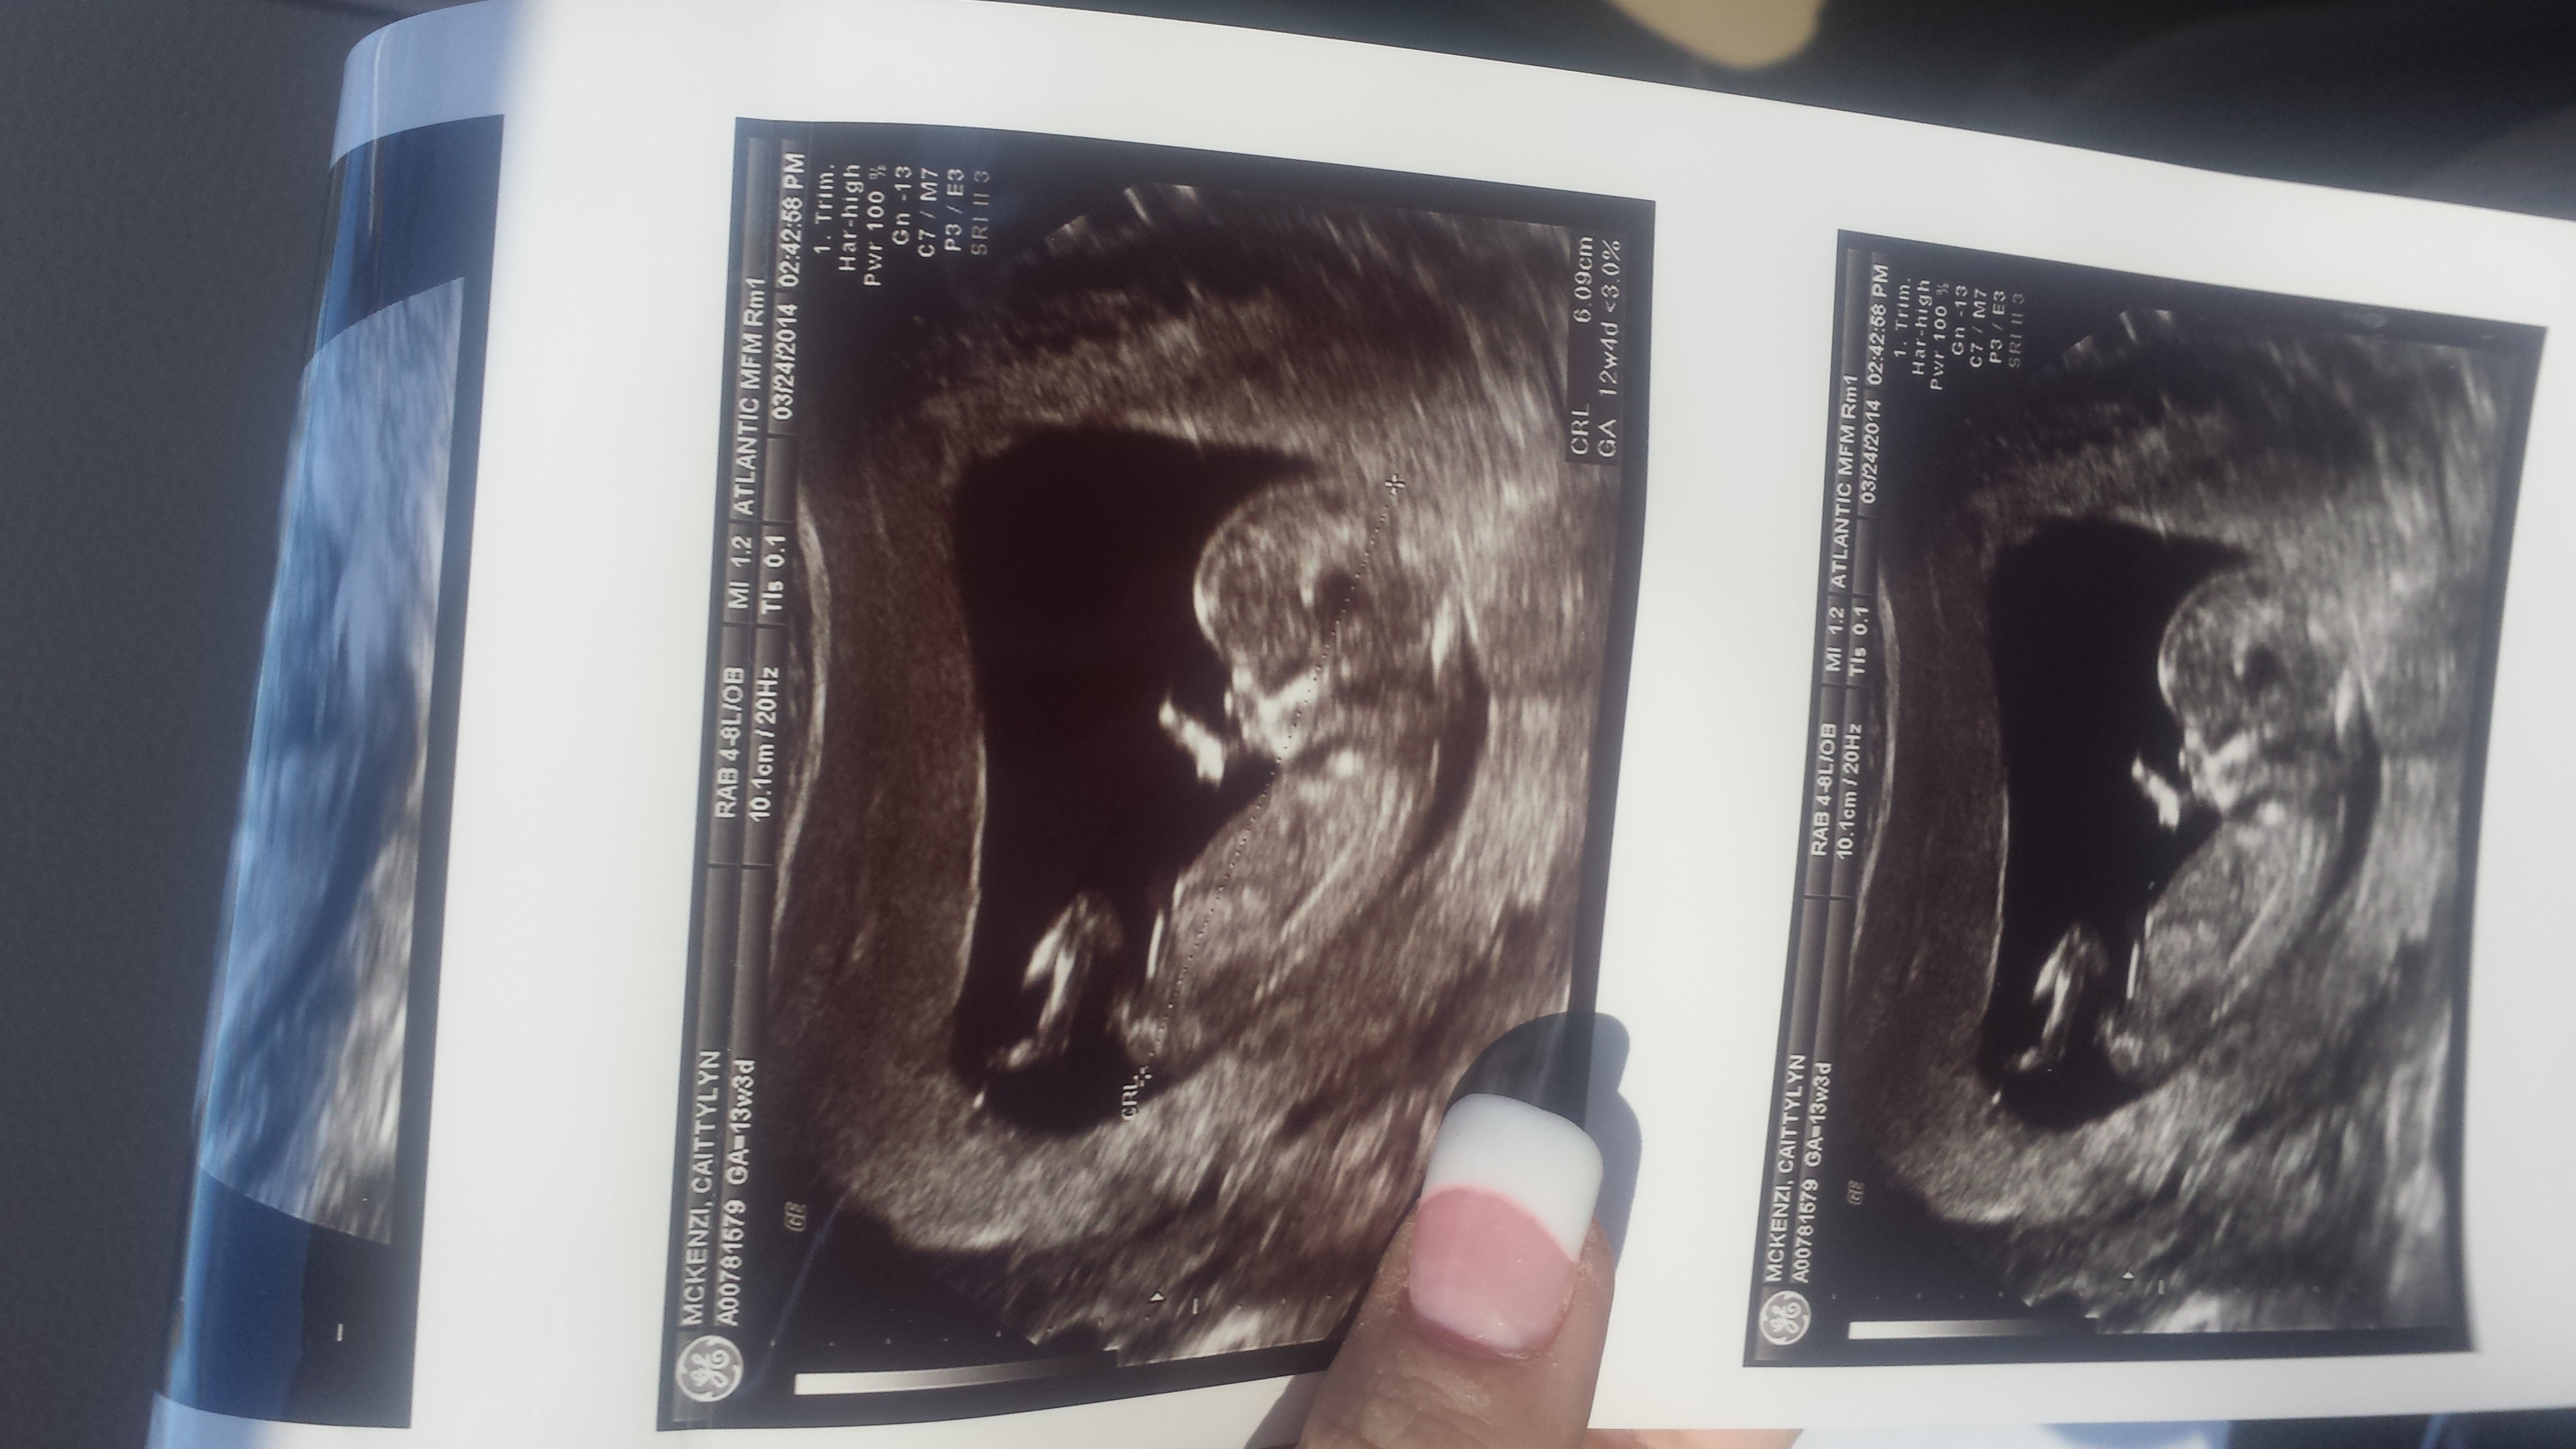

By LMP I should be 13 weeks 2 days but baby is measuring 12 + 4....any nub guesses very appreciated! Attachment 17800Attachment 17801

Thank you all! This is a zoomed rotated pic if its better for guesses....I was kind of hoping girl but having my son have a brother wouldn't be bad either as I see the nub looking boyish too!

Bump. ....when I look quick I see boy....when I zoom in I see girl....this is driving me nuts! Only because on IG I habe gotten girl guesses from their top nub guessers and all boy here. Zooming in on my phone ive done 100000 times. ...wish my nub was a text book nub! Any more guesses appreciated!

Some of the ladies at IG think girl and I got all boy guesses here! Baby is turned up and spine curved so thats why I think im obsessing so much!

I can see why they guess girl. The upper line isn't pointing upwards, but it is really on top of it, like it is placed on it afterward, kwim? The latter being typical for boy nubs.

I think it's a boy, but wouldn't be too surprised as 'he' will turn out to be a 'she'.